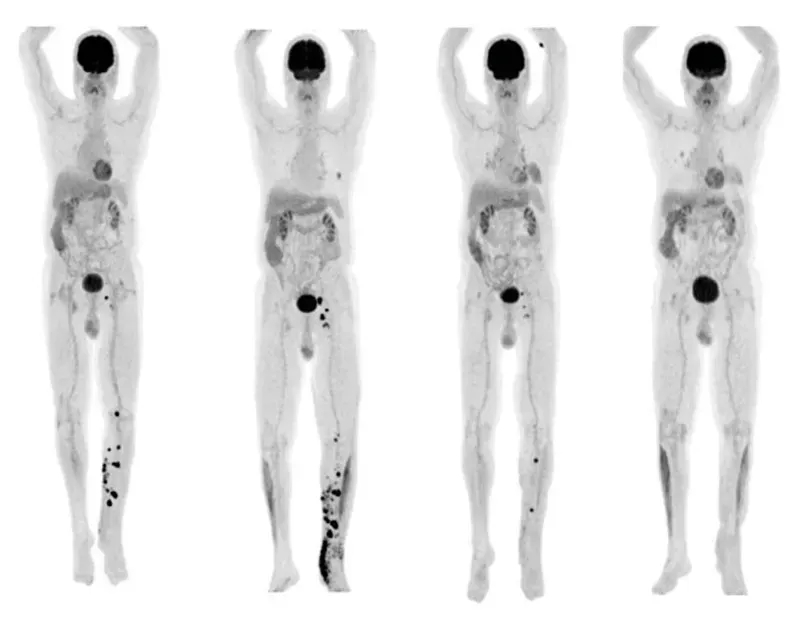

值得一提的是,其中1例更是实现完全缓解(CR),即体内肿瘤全部消失(详见下图)。下图为该完全缓解患者治疗前后的影像学对比:治疗前可见全身多处肿瘤病灶(黑点),治疗后几乎全部消退。

▲图源“Science”,版权归原作者所有,如无意中侵犯了知识产权,请联系我们删除